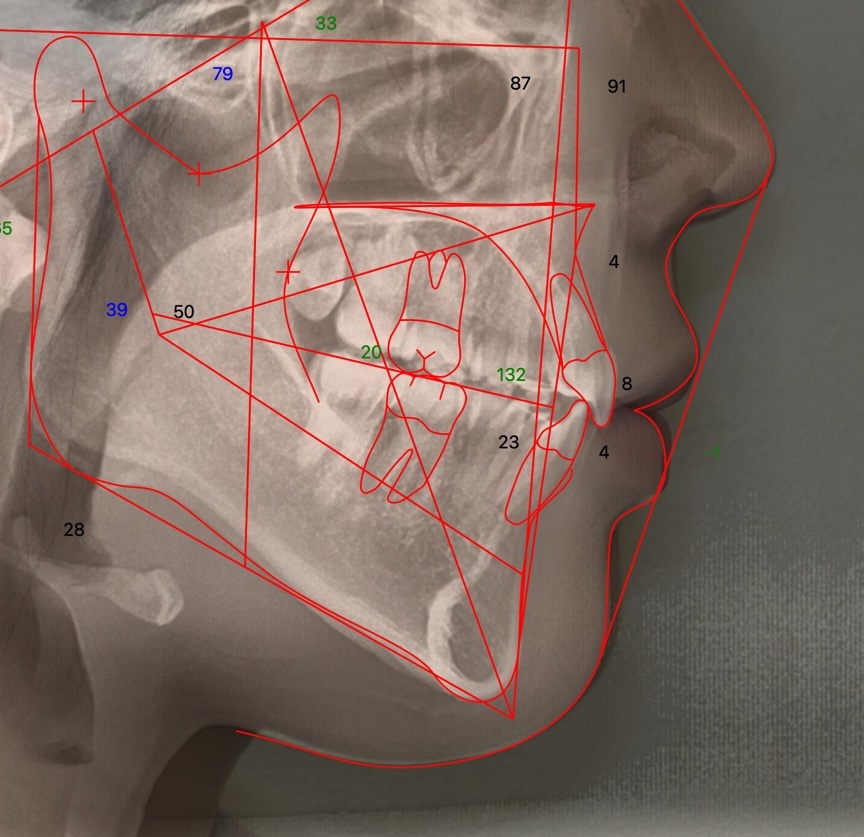

上下顎前突症

口唇突出(口ゴボ)とガミースマイルの症例

| 診断 | 上下前歯の前方突出と上顎骨の下方成長 |

| 治療方針 | 上下左右第一小臼歯の抜歯、親知らずの抜歯。 奥歯の固定や上顎歯列の移動にアンカースクリューを使用。 |